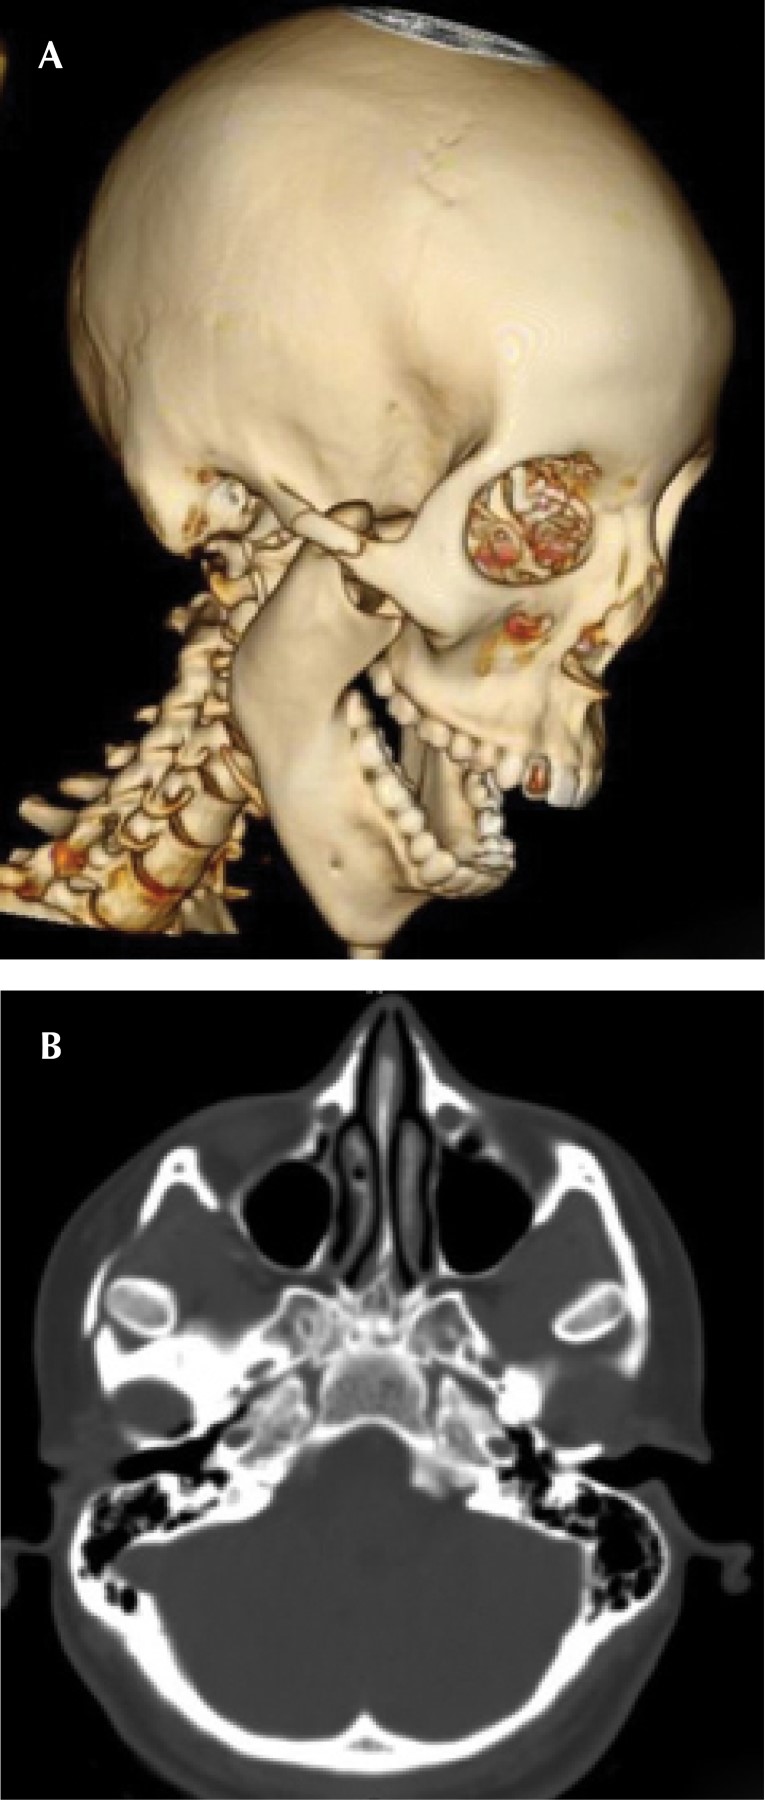

La luxación anterior traumática bilateral de la articulación temporomandibular causa fractura del arco cigomático. Reporte de caso y revisión de la literatura

La luxación anterior bilateral traumática de la articulación temporomandibular es un acontecimiento poco frecuente y en la literatura se describen pocos casos. Aún menos frecuente es la asociación entre luxaciones del cóndilo mandibular y fractura del arco cigomático. El caso presentado describe una luxación anterior bilateral traumática de los cóndilos mandibulares tras un accidente de tráfico con el cóndilo mandibular derecho que causó una fractura del arco cigomático derecho sin presencia de fracturas mandibulares asociadas; a continuación se discute el tratamiento, se revisa la literatura y las posibles causas de este caso inusual.

Figura 1